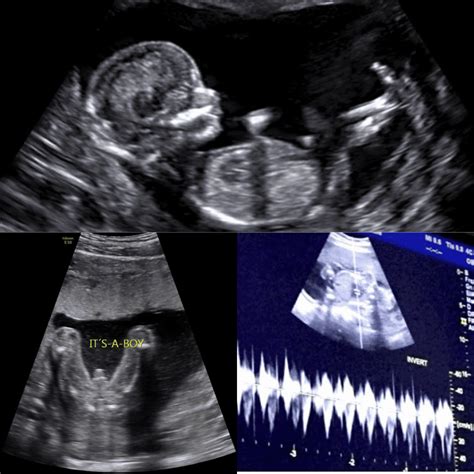

Reaching the midpoint of your pregnancy is a monumental milestone that brings a mix of excitement, nerves, and anticipation. Among the many prenatal appointments on your calendar, the anatomical scan at 20 weeks stands out as one of the most critical. Often referred to as the "mid-pregnancy ultrasound" or the "anomaly scan," this diagnostic procedure provides a comprehensive look at your developing baby’s physical structure and overall health. It is a moment where the abstract feeling of pregnancy becomes startlingly real as you get to see your baby's features, movements, and heartbeat in vivid detail on the screen.

The anatomical scan at 20 weeks is a detailed medical ultrasound performed by a trained sonographer or radiologist. Unlike earlier ultrasounds that may have focused on confirming the pregnancy or dating the gestation, this scan is designed to evaluate every major organ system and physical feature of the fetus. It typically takes between 30 to 60 minutes, depending on the baby's position and how cooperative they are during the process.

During this session, the medical professional carefully measures various parts of the baby’s body to ensure they are growing at the expected rate. They also examine the placement of the placenta, the volume of amniotic fluid, and the umbilical cord to ensure everything is functioning optimally to support your pregnancy.

The primary objective is to confirm that the fetus is developing normally and to identify any structural concerns that might require medical attention after birth. The sonographer systematically reviews several key areas:

• The Brain and Head: Checking for symmetry, the shape of the skull, and the development of the brain structures.

• The Heart: Assessing the four chambers, the valves, and the major vessels leading in and out to ensure proper blood flow.

• The Face: Examining the lips and palate for signs of clefting, as well as the orbits (eye sockets).

• The Spine: Ensuring the vertebrae are aligned and that the skin covers the spine entirely.

• The Abdomen and Internal Organs: Inspecting the kidneys, stomach, liver, and bladder to ensure they are present and functioning correctly.

• Limbs: Counting fingers and toes and ensuring the arms and legs are proportional.